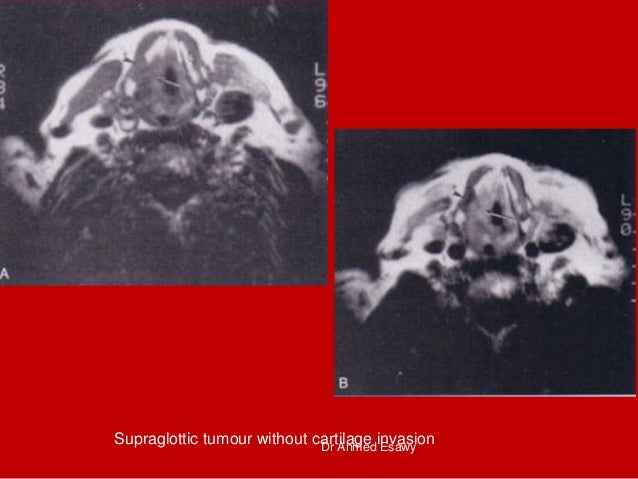

26. 26. Supraglottic tumour without cartilage invasionDr Ahmed Esawy